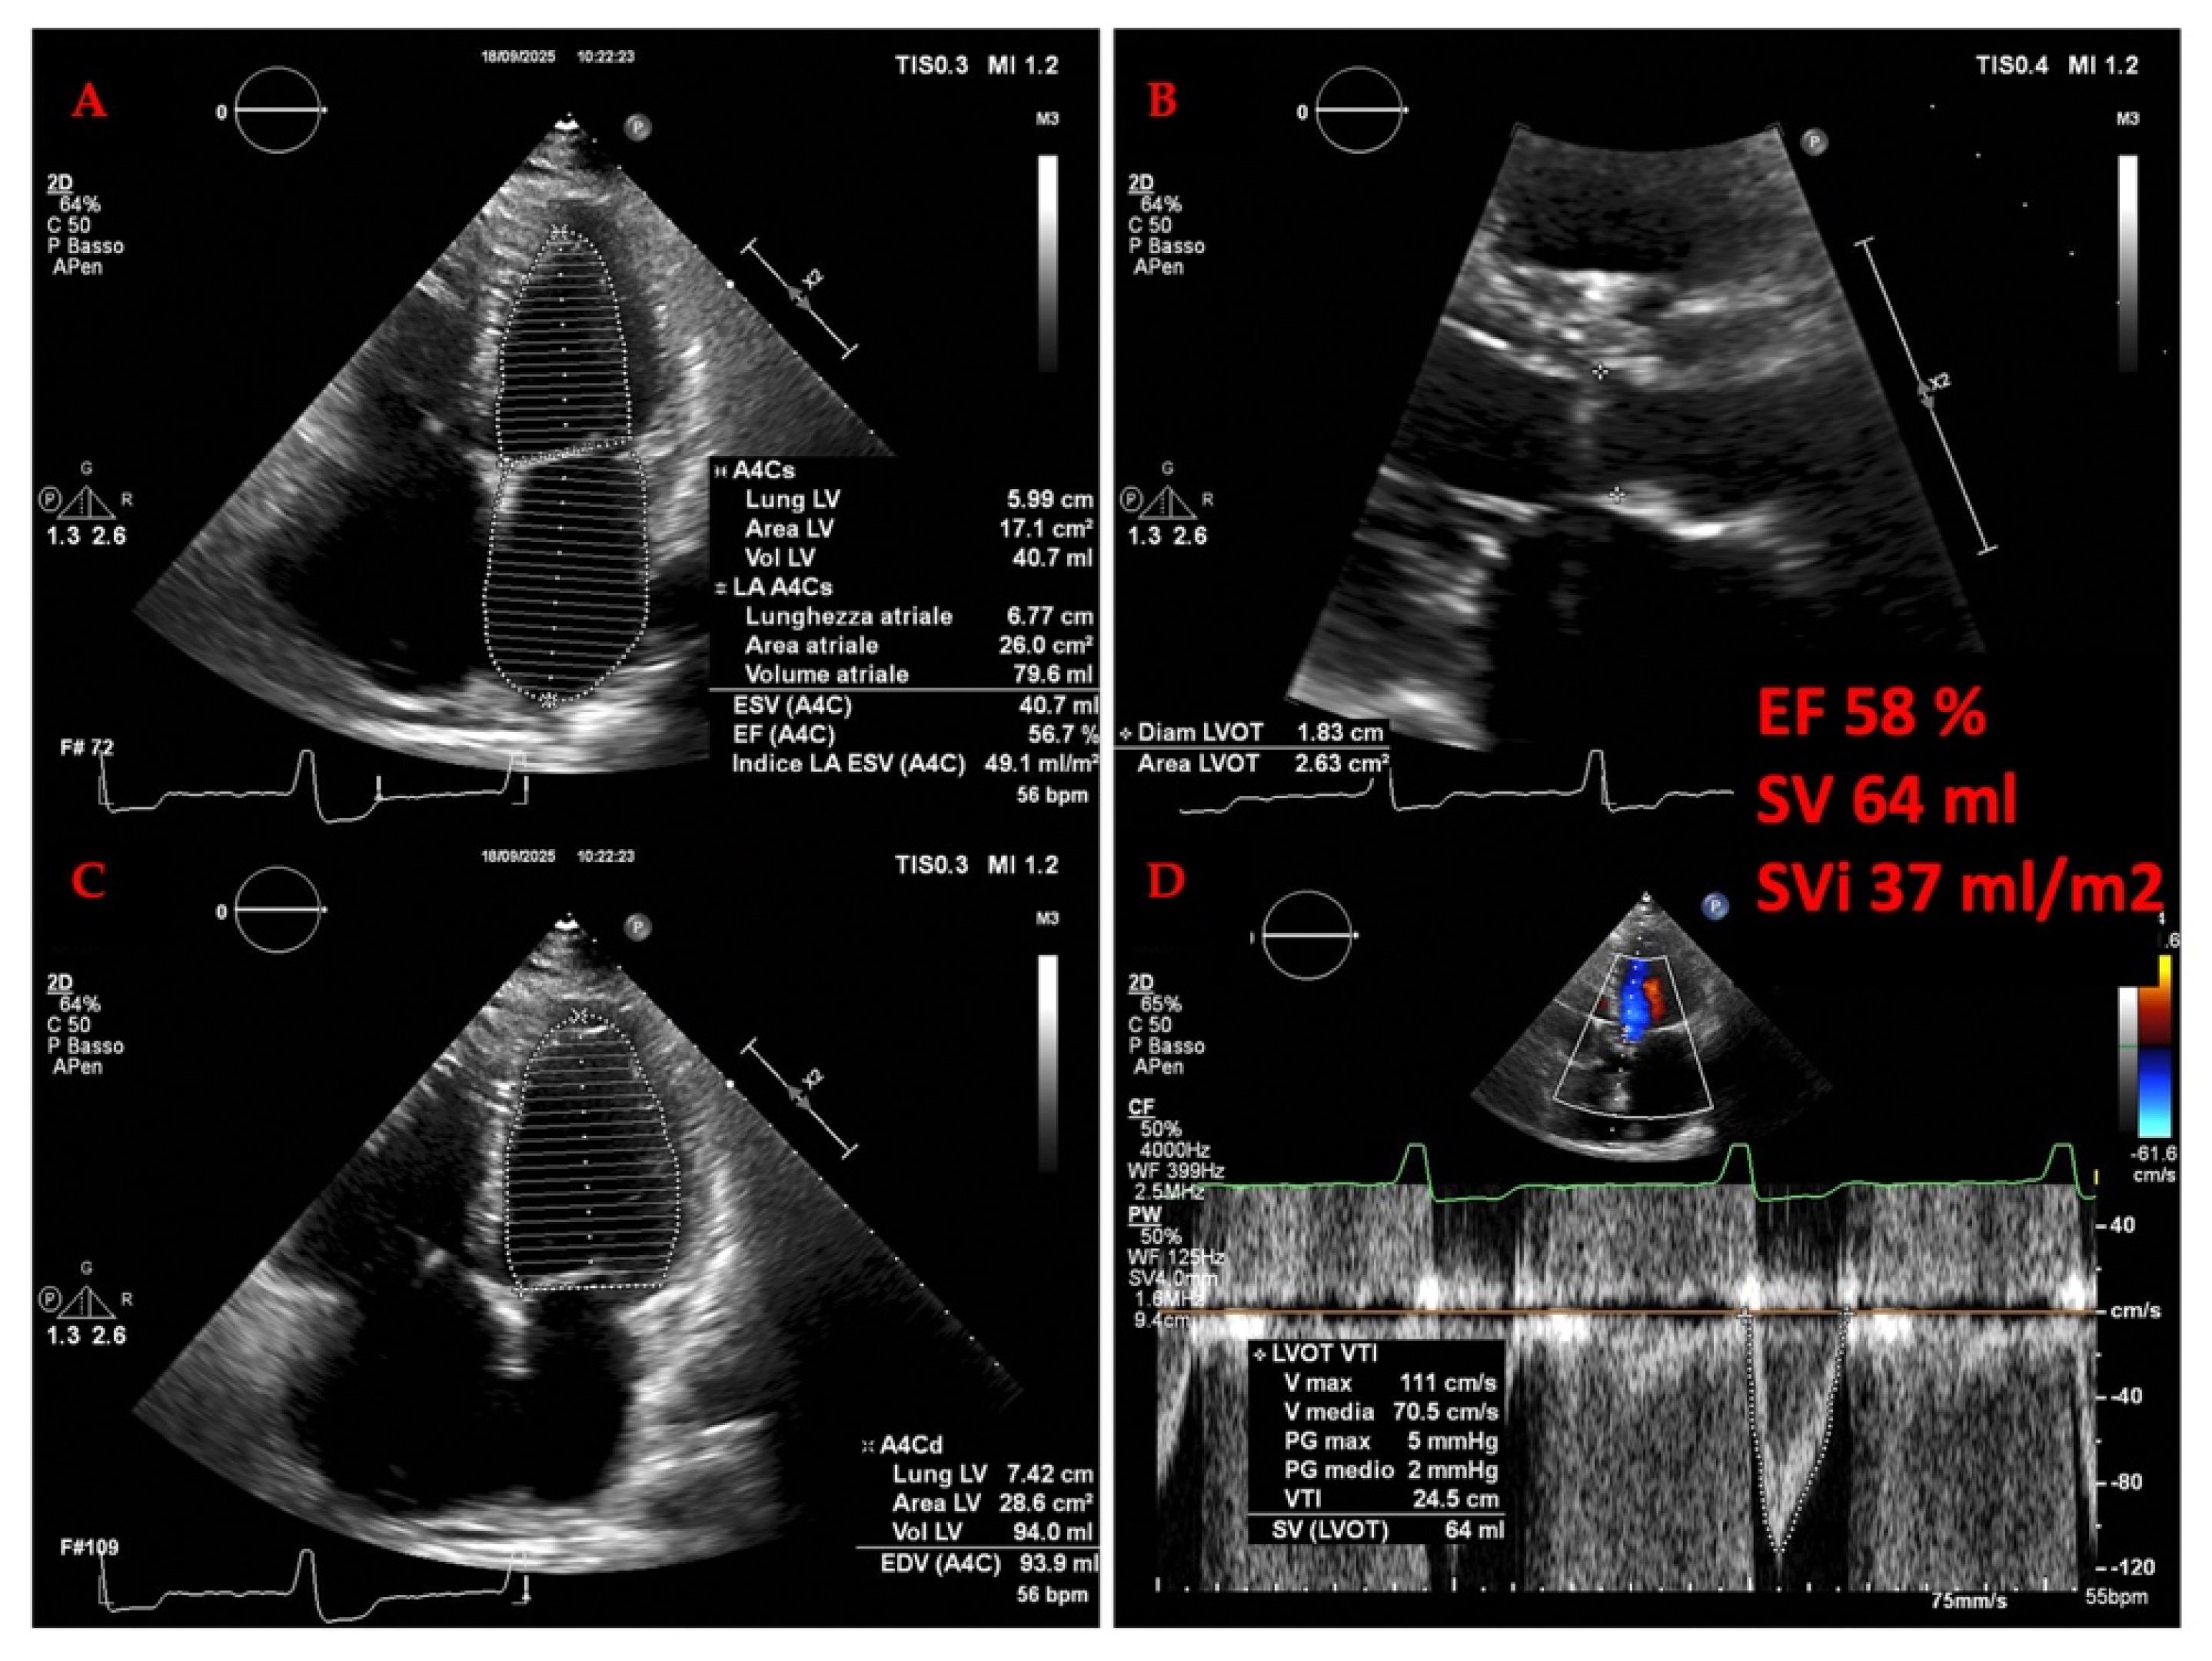

3.2. Cardiac Evaluation: Echocardiography

3.2.1. The Evolving Role of Echocardiography of Left Heart in Heart Failure

3.2.2. The Evolving Role of Echocardiography in Heart Failure: A Focus on the Right Heart and Pulmonary Hypertension (PH)